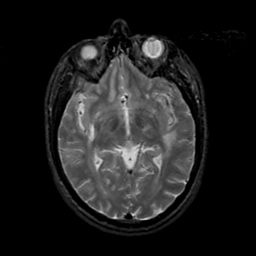

MR Study #19, August 25, 1991 -- Slice #23